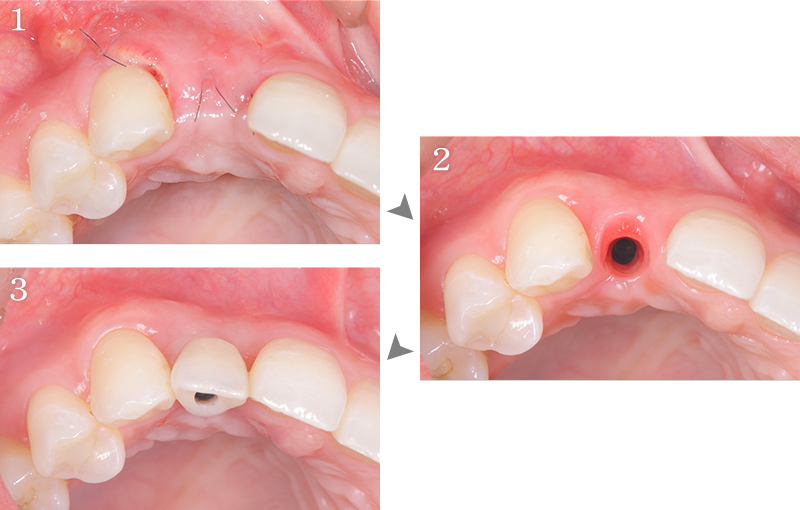

右上前歯部にGBRを併用しインプラント治療を行なった1症例

主訴 右上の前歯に歯を入れたい

治療内容 右上側切歯インプラント、GBR

治療期間 約1年

費用 インプラント埋入手術:27.5万円(税込)

セラミック補綴:22万円(税込)

GBR:11万円(税込)